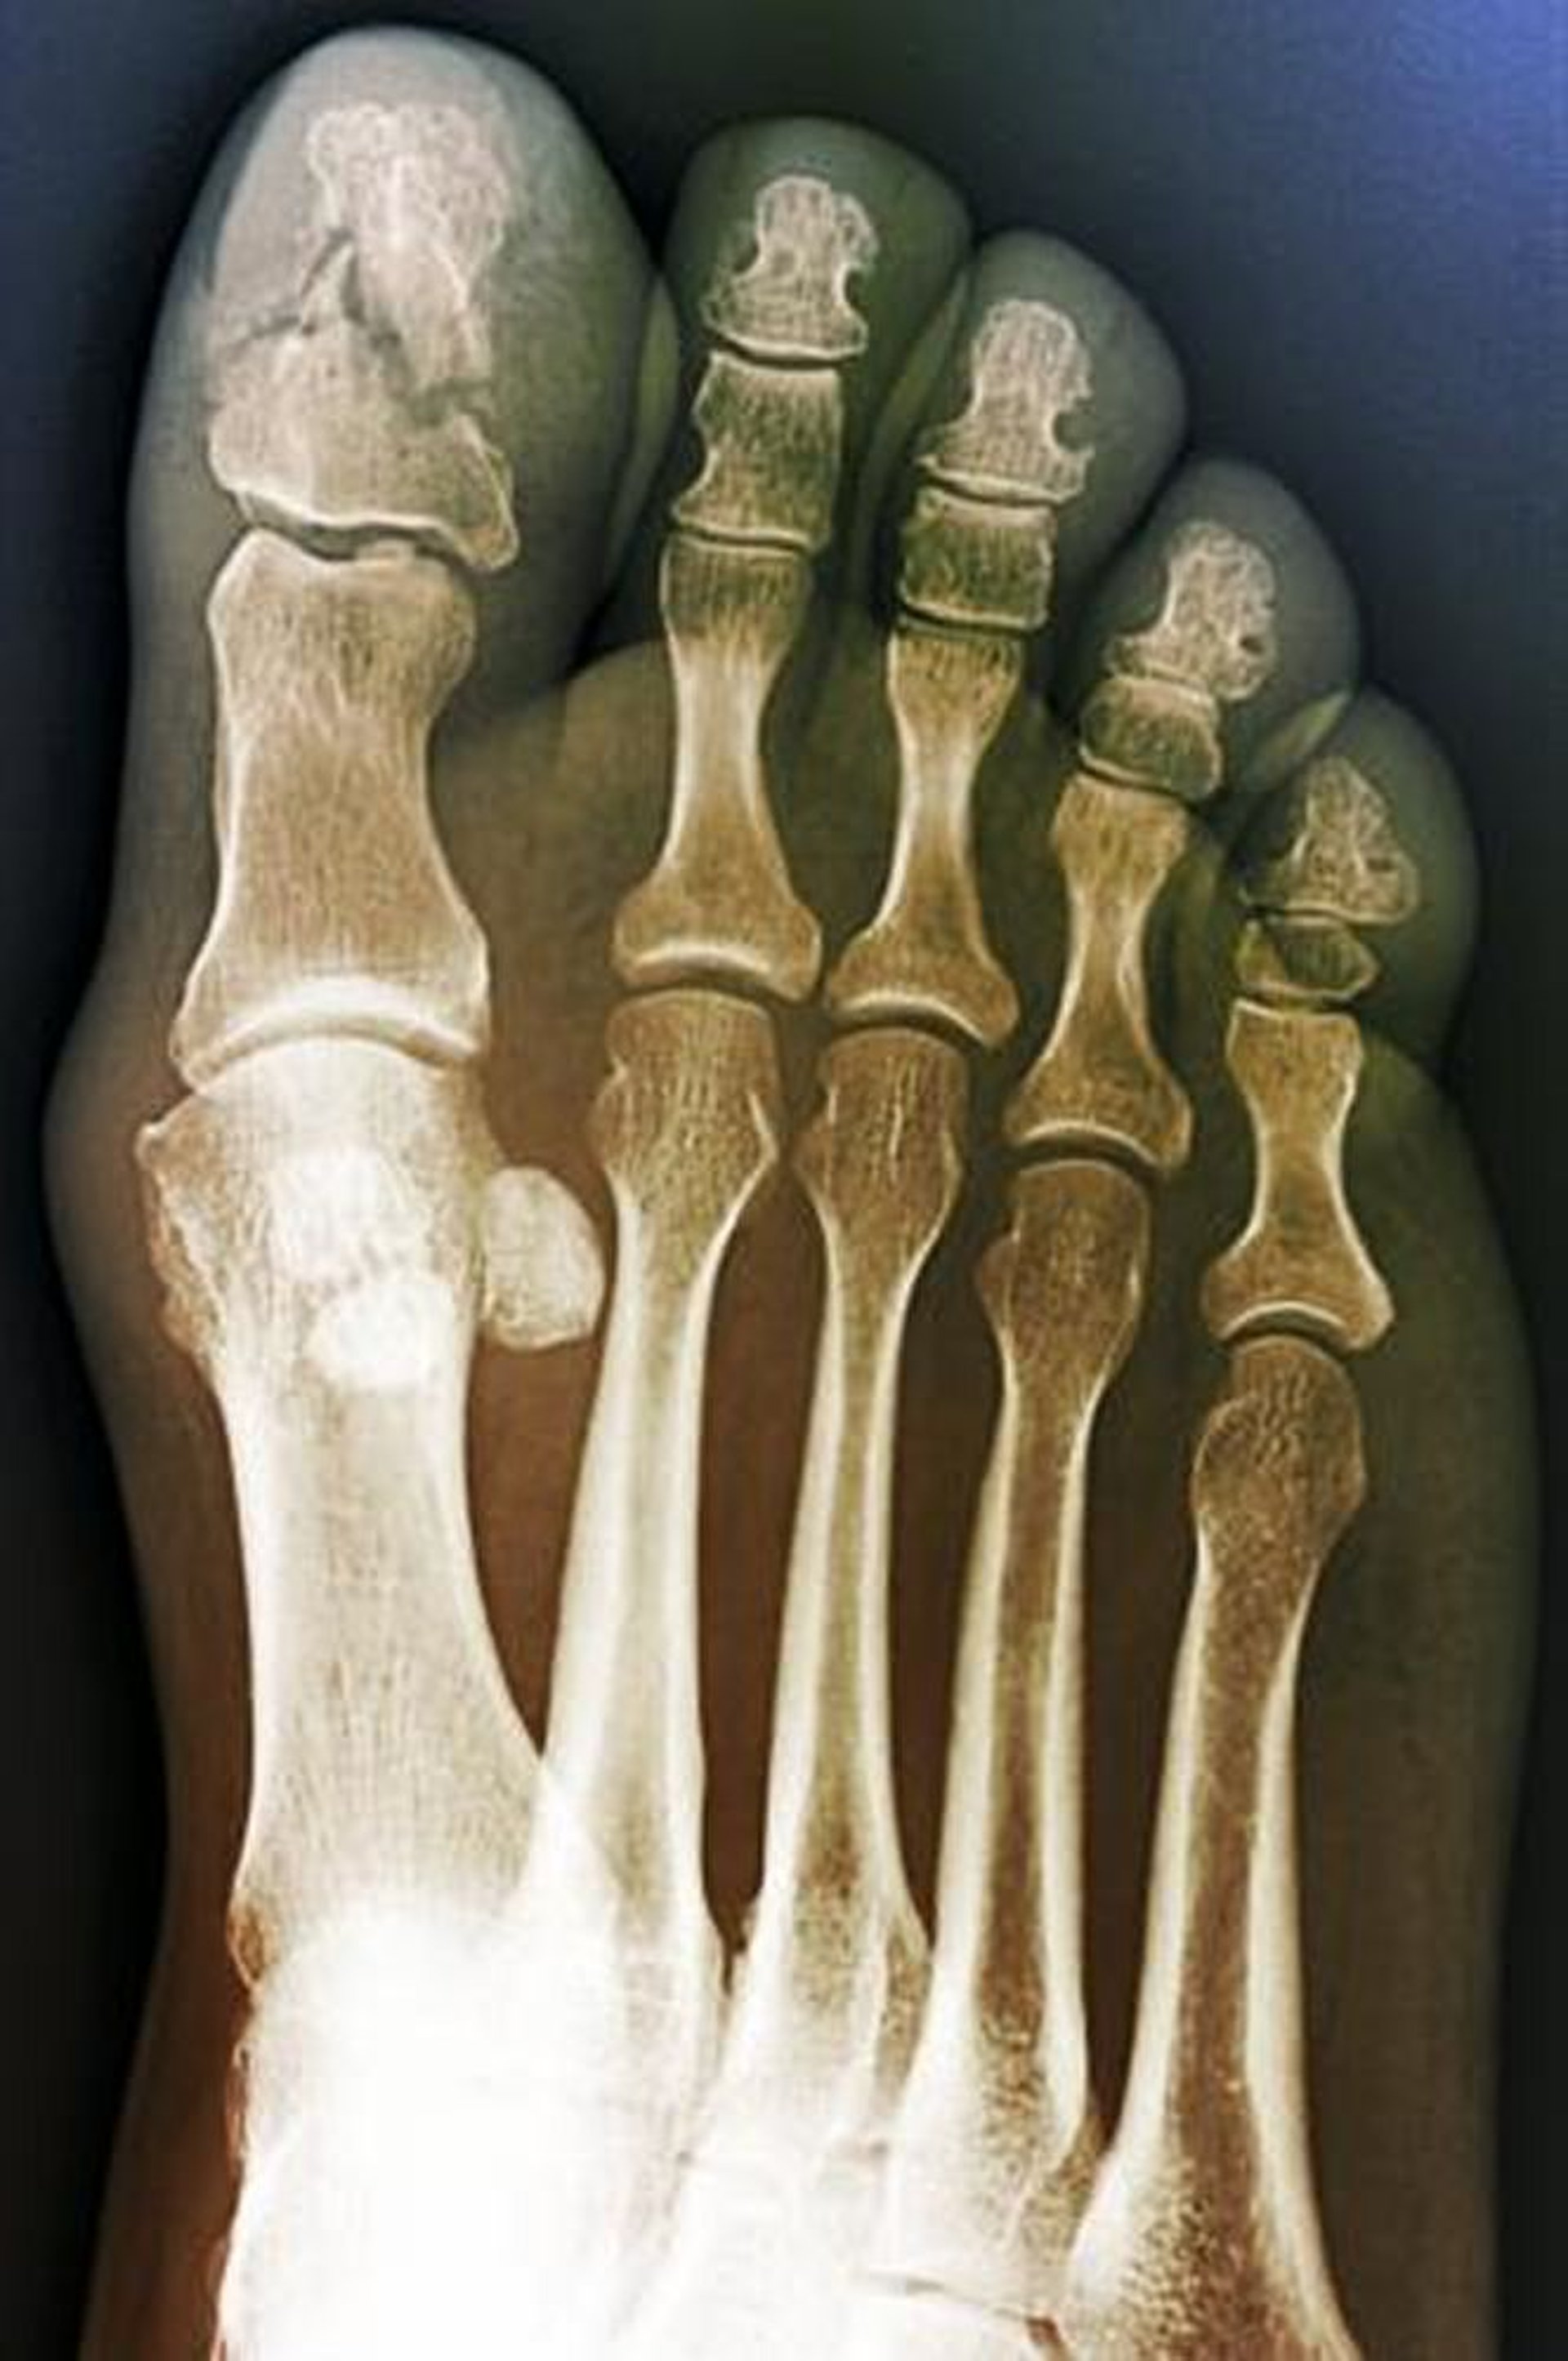

Diese anteroposteriore Ansicht zeigt eine Trümmerfraktur der distalen Großzehenphalanx. Dieser Befund deutet auf einen Quetschungsmechanismus hin.

ZEPHYR/SCIENCE PHOTO LIBRARY

Normalerweise ist die Anfertigung von Röntgenaufnahmen nicht erforderlich, es sei denn, man vermutet eine Rotationsdeformität oder Gelenkbeteiligung oder eine Mitbeteiligung der proximalen Phalanx des großen Zehs (Hallux), weil die Behandlung unabhängig davon, ob eine Fraktur vorliegt oder nicht, dieselbe ist. Wenn Röntgenbilder indiziert sind, werden anteroposteriore, seitliche und schräge Aufnahmen jeder Zehe angefertigt.

Nehmen Sie anteroposteriore, laterale und schräge Ansichten von jedem Zeh, wenn eine Rotationsdeformität oder eine Gelenkbeteiligung vermutet wird oder wenn die proximale Phalanx der Großzehe verletzt ist; andernfalls sind Röntgenaufnahmen in der Regel unnötig, da die Behandlung gleich ist, ob eine Fraktur vorliegt oder nicht.